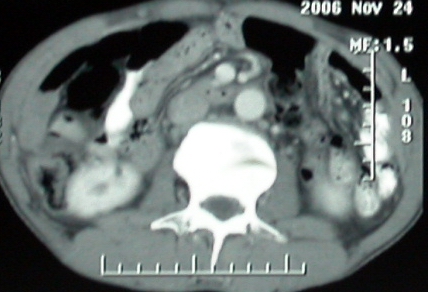

增强ct所见

1、胰头部占位:胰管轻度扩张(可疑双管征),主要考虑恶性肿瘤,胰头癌?十二指肠间质瘤?后腹膜肿瘤?

2、门静脉高压症,主要考虑胰头部肿块压迫或者浸润所致肝前性门静脉主干受压;肝功能尚可,脾脏不大,无脾亢;

3、胆囊积液、肝胆管积气、胆道扩张伴有胆道感染;

4、右肝后上段占位(考虑肝胆管结石伴肝组织萎缩?)

5、下腔静脉受压;

6、左半肝缺失,原因不明?

ct表现:1,胰腺钩突后方肿块,不均强化,中心密度低,钩突及门静脉前移。2:肝右后叶不均强化灶,突出肝表面,3:胆囊明显增大,肝内胆管及肝总管内积气。4:腹腔内少量积液。